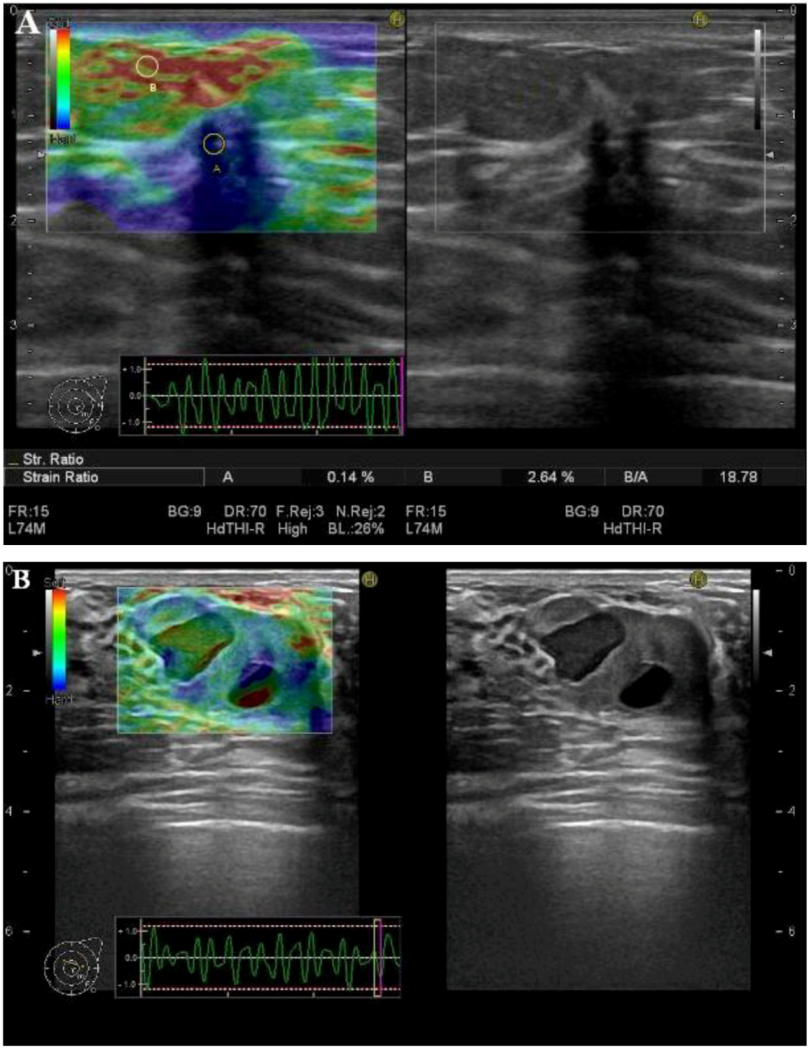

3.3. SR-Measurements